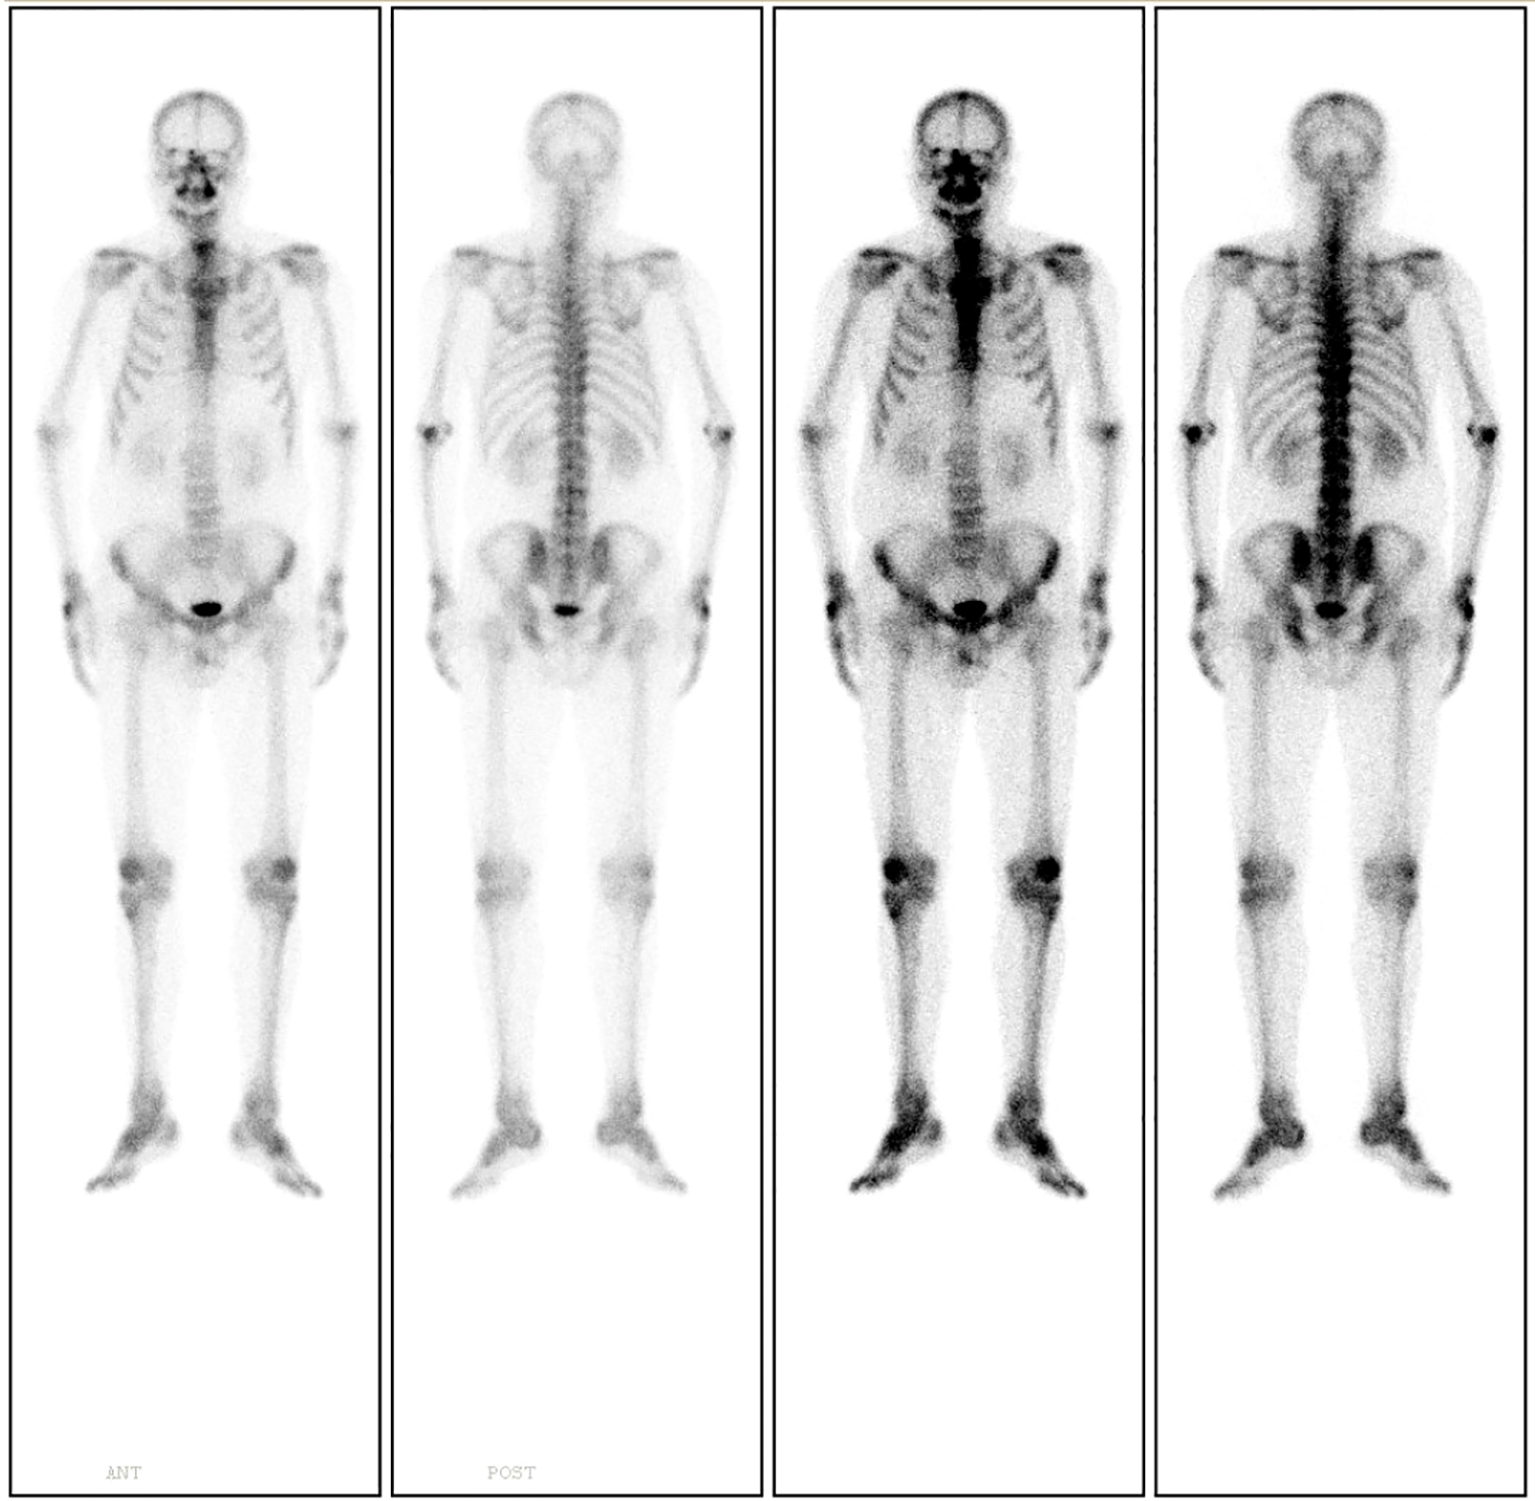

18F-Fluorodeoxyglucose Positron Emission Tomography-Computed Tomography (18F-FDG PET-CT) imaging demonstrated mild metabolic activity within the nodule, exhibiting a maximum standardized uptake value (SUVmax) of 2.4 (Figure 2). The imaging findings were indeterminate between granulomatous inflammation and neoplastic lesions, necessitating histopathological confirmation via biopsy. Whole-body bone scintigraphy using emission computed tomography (ECT) revealed no evidence of pathological skeletal lesions (Figure 3). All laboratory parameters were within normal limits: negative for lung cancer biomarkers (CEA, NSE, CYFRA 21-1, ProGRP) and unremarkable hematological/inflammatory profiles (WBC, neutrophils, CRP, ESR).

Figure 3

Whole-body bone scintigraphy using ECT demonstrates no evidence of pathological skeletal lesions.